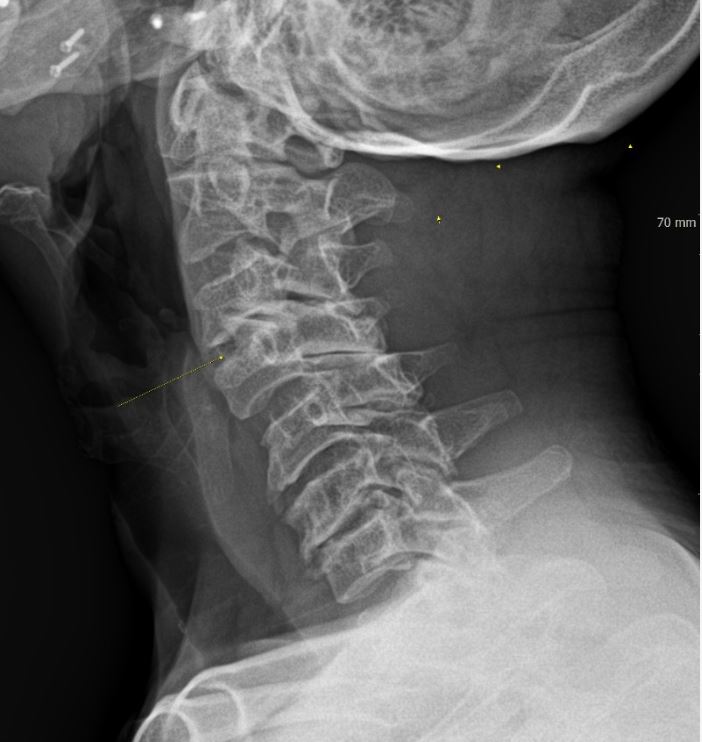

목디스크란 목뼈 사이에 있는 디스크가 손상되어 신경을 압박하는 질환을 의미합니다. 디스크는 젤리와 같은 수핵과 섬유륜으로 구성되어 있습니다. 섬유륜이 손상되면 수핵이 밖으로 밀려나와 신경을 압박하게 됩니다.

목디스크는 주로 잘못된 자세, 과도한 스트레스, 외상 등으로 발생합니다. 잘못된 자세로 장시간 컴퓨터를 사용하거나 운전을 하면 목에 무리가 가고 디스크가 손상될 수 있습니다.

또한 과도한 스트레스는 근육을 긴장시켜 디스크에 손상을 줄 수 있습니다. 외상은 교통사고, 운동 중 충격 등으로 목뼈가 부러지거나 골절되면 디스크가 손상될 수 있습니다.